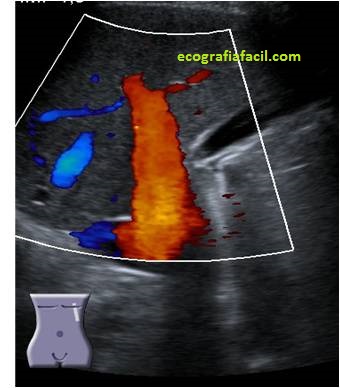

Os voy a dejar una serie de imágenes, quiero que observes como desde la imagen 1 a la imagen 7 el paso del tiempo ha ido cambiando este modo de trabajo, como el avance tecnológico ha ido modelando estos modos de trabajo Doppler en una misma ecoarquitectura muy estudiada como la vena porta en su acceso transcostal, mira:

La imagen 1 era la de un muy buen equipo cuando yo empecé, la imagen 7 es la mejor que he visto hasta hoy día.

La imagen 2 y 3 fue nuestro día a día eco tras eco…doppler color y doppler power, durante años modos de trabajo muy usados, cada vez más, cada vez aportaban más información, un buen doppler siempre habla bien de un equipo de ecografía. Si quieres repasar los conceptos básicos de del Doppler que nos contó Alejandro te lo enlazo para que puedas revisarlo, él es el experto en Doppler y te lo cuenta genial.

Básicamente te cuento que hemos usado el doppler durante décadas para detectar el flujo de los vasos y su velocidad, para ver lesiones y como están vascularizadas, incluso para detectar litiasis. Buscamos flujos rápidos (doppler color) o flujos más lentos (doppler power)…Hoy en día estudiamos estructuras que requieren implementar su estudio con otras técnicas, en ocasiones, para ver cómo es la vascularización de algunas lesiones debemos emplear el contraste ecográfico, por ejemplo.